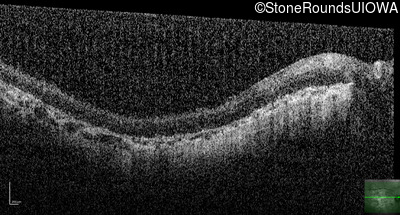

Optical Coherence Tomography - Right - Hand Motion @ face sc

Exemplar / OCT Stack